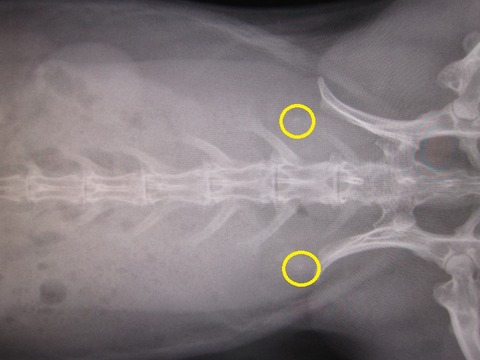

kagu0812

無いんちゃう?」

kagu0813

「な 先生、無いやんね無いやんね

というか、かぐらさんお腹周りが大きいなと思ってたら

脂肪も多いです…(。--)ノ (上下外側の色の薄い部分…)

ただ、強いてこじつけレベルで指摘するとしたら…こうゆう白い塊ね。

kagu0811

これは左右対象にあるから恐らく乳頭と思われる… それと、

kagu0810

…印付けに自信がないですが、薄いおはじきのような白色は写ってます。

上にいくと消化器官ですが、丸くなる手前かも、とかとか…

…ちょっとモヤっと感は残るんですが、

「喜んでも良いと思います」て言うてたから、喜んでいいんやと思います(^-^;)